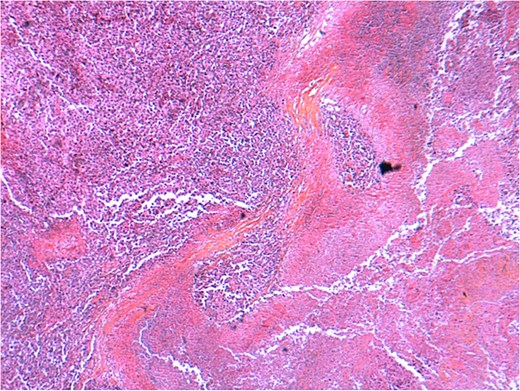

Microscopic evaluation revealed a poorly differentiated neoplasm composed of pleomorphic cells arranged in solid sheets and nests, with high nuclear-cytoplasmic ratio, prominent nucleoli, and brisk mitotic activity. Extensive necrosis was present. Immunohistochemical staining was positive for cytokeratin AE1/AE3 and vimentin, while negative for CK7, CK20, HepPar-1, and chromogranin, supporting the diagnosis of undifferentiated carcinoma. Vascular emboli were identified, and residual tumor cells were present at the resection margin, consistent with an R1 resection. The tumor was staged as pT3NxMx (Figs 5–8).

Histopathological examination of the gallbladder tumor (H&E stain) showing a highly undifferentiated carcinoma with extensive necrosis and inflammatory infiltrates. The tumor exhibits irregular architecture with areas of stromal reaction and vascular invasion.